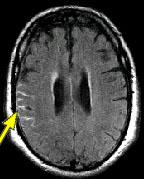

IMAGING FINDINGS: The CT was performed on AIC’s new 16-slice helical multi-slice CT (MSCT). Both routine single-slice and thin-section helical scans were obtained and 3D/Multiplanar images were performed on the Advanced 3D workstation. Fig. 1 shows an image at the level of the lateral ventricles with possible high density within the sulci on the right (arrow). To confirm this finding, an MRI with contrast was then obtained on AIC’s 1.5-Tesla high-field, short-bore Siemens MRI. Fig. 2a-b are T2-weighted images at the same level showing NO definite abnormality. T1-weighted images (not shown) were also negative. The post-contrast images (not shown) showed NO abnormal enhancement in this region, either. Diffusion-weighted images were also negative. However, Fig. 3a-b, which are FLAIR images, demonstrate clear hyperintensity within multiple sulci involving the right temporo-parietal area (arrows).

DIAGNOSIS: The FLAIR images are compatible with Subarachnoid disease. The Differential Diagnosis includes: (1) Subarachnoid Hemorrhage (SAH); (2) Meningitis; (3) Infarct; (4) Flow Artifact. Lack of enhancement is against meningitis. Acute infarct was ruled out on the basis of negative Diffusion MRI and lack of cytotoxic edema on the FLAIR images. Focal abnormality is against flow artifact (which is more diffuse and usually in the posterior fossa on FLAIR images). The clinical history of trauma and the high-density on CT and hyperintensity on FLAIR images within the sulci are diagnostic of Acute Post-traumatic Subarachnoid Hemorrhage (SAH).